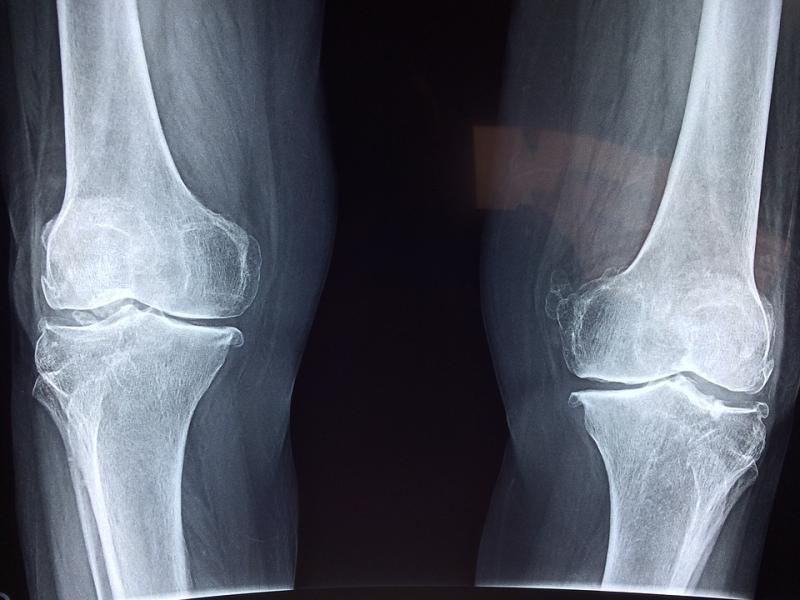

€900,000 has been allocated to upgrade x-ray equipment at four Donegal Community Hospitals.

The new equipment will be installed in Dungloe, Killybegs, Donegal Town and Carndonagh. X-ray facilities have also been added at the Ballyshannon Health Campus.

The community x-ray service was first developed over 30 years ago as part of a strategy to provide timely and accessible services to rural populations.  The existing community x-ray facilities will now be upgraded with modern digital x-ray equipment which will be linked with Letterkenny and Sligo University Hospitals.

Deputy McHugh added: “This new equipment will mean these rural communities will have access to the very latest x-ray equipment which will mean they don’t have to travel to Letterkenny or Sligo for x-ray. The x-rays will be sent electronically to the hospitals where they will be read and reported on by Consultant Radiologists, the reports will then be sent back to the patient’s GP.”